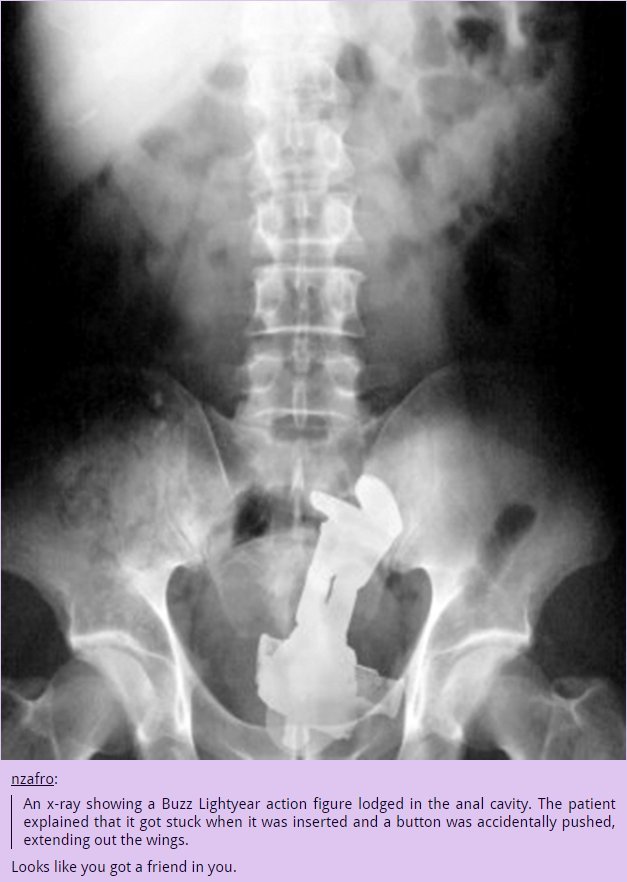

PM ' g a Buzz attic's figure in the anal cavity. The patient

that it get stuck when it was inserted and a butter": was accidentally pushed,

eat the wings.

Leeks like you get 'a"' friend in yen.